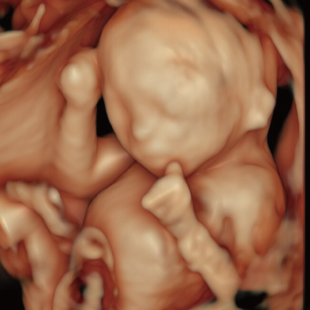

妊娠中期になると、胎児の体や内臓の構造がよりはっきりと確認できるようになります。 中期スクリーニングでは、頭部、顔面、頸部、胸部、腹部、心臓、手足、外性器、臍帯や胎盤など、全身をくまなく観察し、形態の状態を詳しく確認します。この頃に染色体数の変化を疑わせる所見が確認される事もあります。

胎児ドックの様子_中期_頭 胎児ドックの様子_中期_顔面 胎児ドックの様子_中期_心臓 胎児ドックの様子_中期_腹部 胎児ドックの様子_中期_足 胎児ドックの様子_中期_4D